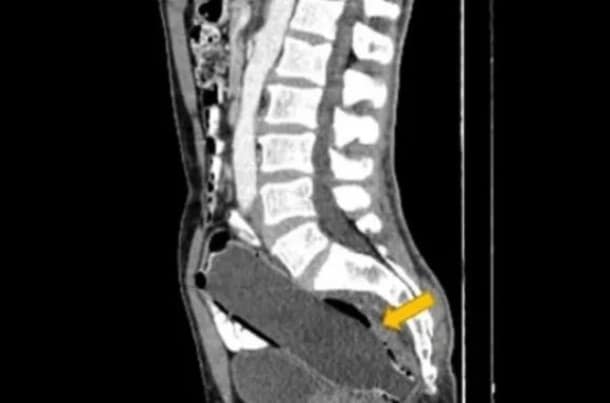

O objeto foi encontrado na região pélvica do paciente, a 10 milímetros da abertura do ânus, e estava alocada entre o reto e o cólon, que faz parte do intestino grosso.